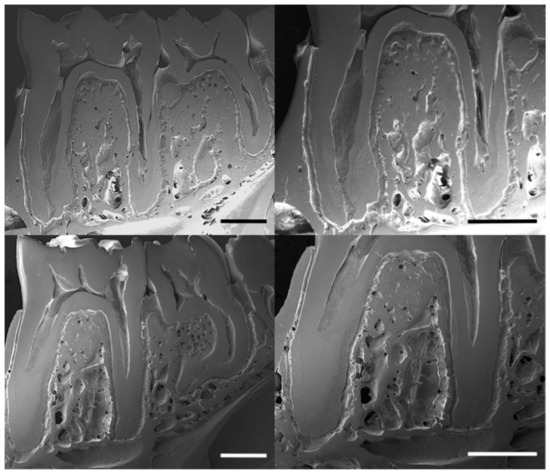

The scanning electron images show the trabecular distribution of alveolar bone in the control and lead-exposed groups (Figure 3). These images display the bone structure of the mandible and the enlarged view of the first molar inter-radicular region. A relative decrease in trabecular bone distribution and higher porosity were observed in the lead-exposed group compared with the control group.

Figure 3. Scanning electron micrographs (SEM) showing the microstructural changes of alveolar bone in buccal axial cross-sections of rat mandibles in the control (upper row images) and lead-exposed (lower row images) groups. Scale bars: 1 mm.

Micro-CT analyses allow the study of morphological changes at the micro-architectural level in bone health and disease [32]. Here, we focused on the characterization of the trabecular organization in the alveolar bone region, as it constitutes the main structure in this specific non-weight bearing bone [1]. Moreover, alveolar bone is clinically quite important, as it represents the most metabolically active type of bone involved in dentition development [2]. The micro-CT results in the current research showed a significant decrease in the bone mineral density (BMD) and bone volume to tissue volume ratio (BV/TV) in the trabecular bone of lead-exposed rats compared with the control group. SEM images also confirmed this impairment in the trabecular structure of the alveolar bone. These observations showed higher porosity and a decrease in trabecular density in the lead-exposed group, particularly in the inter-radicular region of the mandibular molars. Previous studies showed the effect of lead exposure on decreased bone density in both cortical and trabecular bone in rat femurs [10,33]. These effects indicate a similar mechanism of bone maturation normally associated with osteoporosis [34,35]. In fact, the decrease of the trabecular microarchitecture characteristics in alveolar bone has been related to increased incidence of osteoporosis and risk of fractures [35,36,37]. Furthermore, the trabecular bone in the alveolar region showed a decrease in the number of trabeculae in the lead exposure group. Similar alterations have been reported in osteoporosis, in which a marked reduction of the trabecular bone volume, as well as a reduction in the thickness and number of trabecular, was observed [32,38]. The process of bone remodelling comprises a number of cellular events in which trabecular sites, due to their high surface-to-volume ratio, were more commonly affected by the dysregulation in bone turnover processes [39]. The alteration of the bone metabolism caused by lead exposure [6,40] may be related to the deterioration of the trabecular characteristics in alveolar bone, which resembles bone mineral loss [33]. Moreover, mineral alterations in the alveolar region are associated with a physiological disorder that can lead to a structural disorder with important mechanical implications.